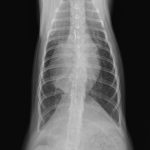

先天性心嚢横隔膜ヘルニア

若い猫が、普段はとても元気だけど、遊んだ後などに咳をする。呼吸が早くなる時がある。などの呼吸器症状で主治医を受診しました。エックス線検査の結果、心嚢横隔膜ヘルニアと診断されました。主治医より、外科的な対応のため紹介受診となりました。腹部正中切開の後、心嚢内に逸脱した、肝臓、胆嚢、小腸を腹腔内に戻し、横隔膜を再建しました。術後には、再拡張性肺水腫という病態が発生する可能性があるため、24時間体制で、患者さんを見守ります。幸い、肺水腫の傾向はみられず、5日目に無事に退院となりました。周術期には一時的に低酸素症に陥ったり、二酸化炭素濃度が上昇したりと、不安定な場面もありましたが、小さな体で本当によく頑張ってくれました。これで、普通の子猫としてどんどん大きく成長してくれると思います。本当によかった。